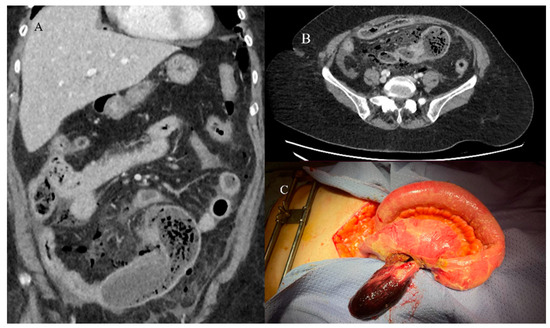

- Marsicovetere, P.; Ivatury, S.J.; White, B.; Holubar, S.D. Intestinal intussusception: Etiology, diagnosis, and treatment. Clin. Colon. Rectal Surg. 2017, 30, 30–39. [Google Scholar] [CrossRef] [PubMed]

- Kim, Y.H.; Blake, M.A.; Harisinghani, M.G.; Archer-Arroyo, K.; Hahn, P.F.; Pitman, M.B.; Mueller, P.R. Adult intestinal intussusception: CT appearances and identification of a causative lead point. Radiographics 2006, 26, 733–744. [Google Scholar] [CrossRef]

- Panzera, F.; Di Venere, B.; Rizzi, M.; Biscaglia, A.; Praticò, C.A.; Nasti, G.; Mardighian, A.; Nunes, T.F.; Inchingolo, R. Bowel intussusception in adult: Prevalence, diagnostic tools and therapy. World J. Methodol. 2021, 11, 81. [Google Scholar] [CrossRef] [PubMed]